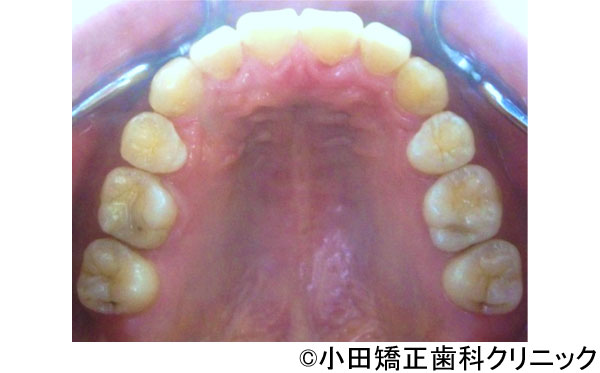

【症例3】呼吸から治して厳しいでこぼこ状態ではあるが、歯を抜くことなくしかも突出のない知的な口元に改善する治療

- 治療前

- 治療後

- 治療名

- 呼吸から治して厳しいでこぼこ状態ではあるが、歯を抜くことなくしかも突出のない知的な口元に改善する治療

- 患者様

- 9歳

- 費用

- 1,000,000円(税込)(永久歯治療を含む)

- 期間

- 早期治療2年+永久歯治療1年

治療内容

-

患者様の症状

厳しい上下歯列のでこぼこ不十分な鼻呼吸のため口呼吸が必要となり、舌、唇などの筋肉の良くない動き、つまり舌が、本来、飲み込むために上あごに引っ付くのではなく、下に下がり、口が開くことで頬が締まって上歯列は狭くなります。また下に下がった下の圧力で下歯列も内側に倒れて狭い舌歯列となります。

鼻呼吸不十分による口呼吸がもたらす締まりにかけるやや突出した口元、不適切な姿勢、免疫機構の不善によりもたらされる過大な感染症のリスク -

治療法

上歯列に固定式の拡大装置により左右の上あごの接合部を拡げて鼻呼吸に改善する。舌が収まる空間を得るために下歯列にも特殊な拡大装置により歯を支える骨の付け根からしっかりと広げる。

治療結果

美しい口元、顔立ち、健康的な呼吸をもたらし、鼻呼吸を導く徹底した従来より効果の大きい広げる装置により、厳しいでこぼこ状態を歯を抜くことなく、しかも突出の全くないきれいな口元に改善しました。